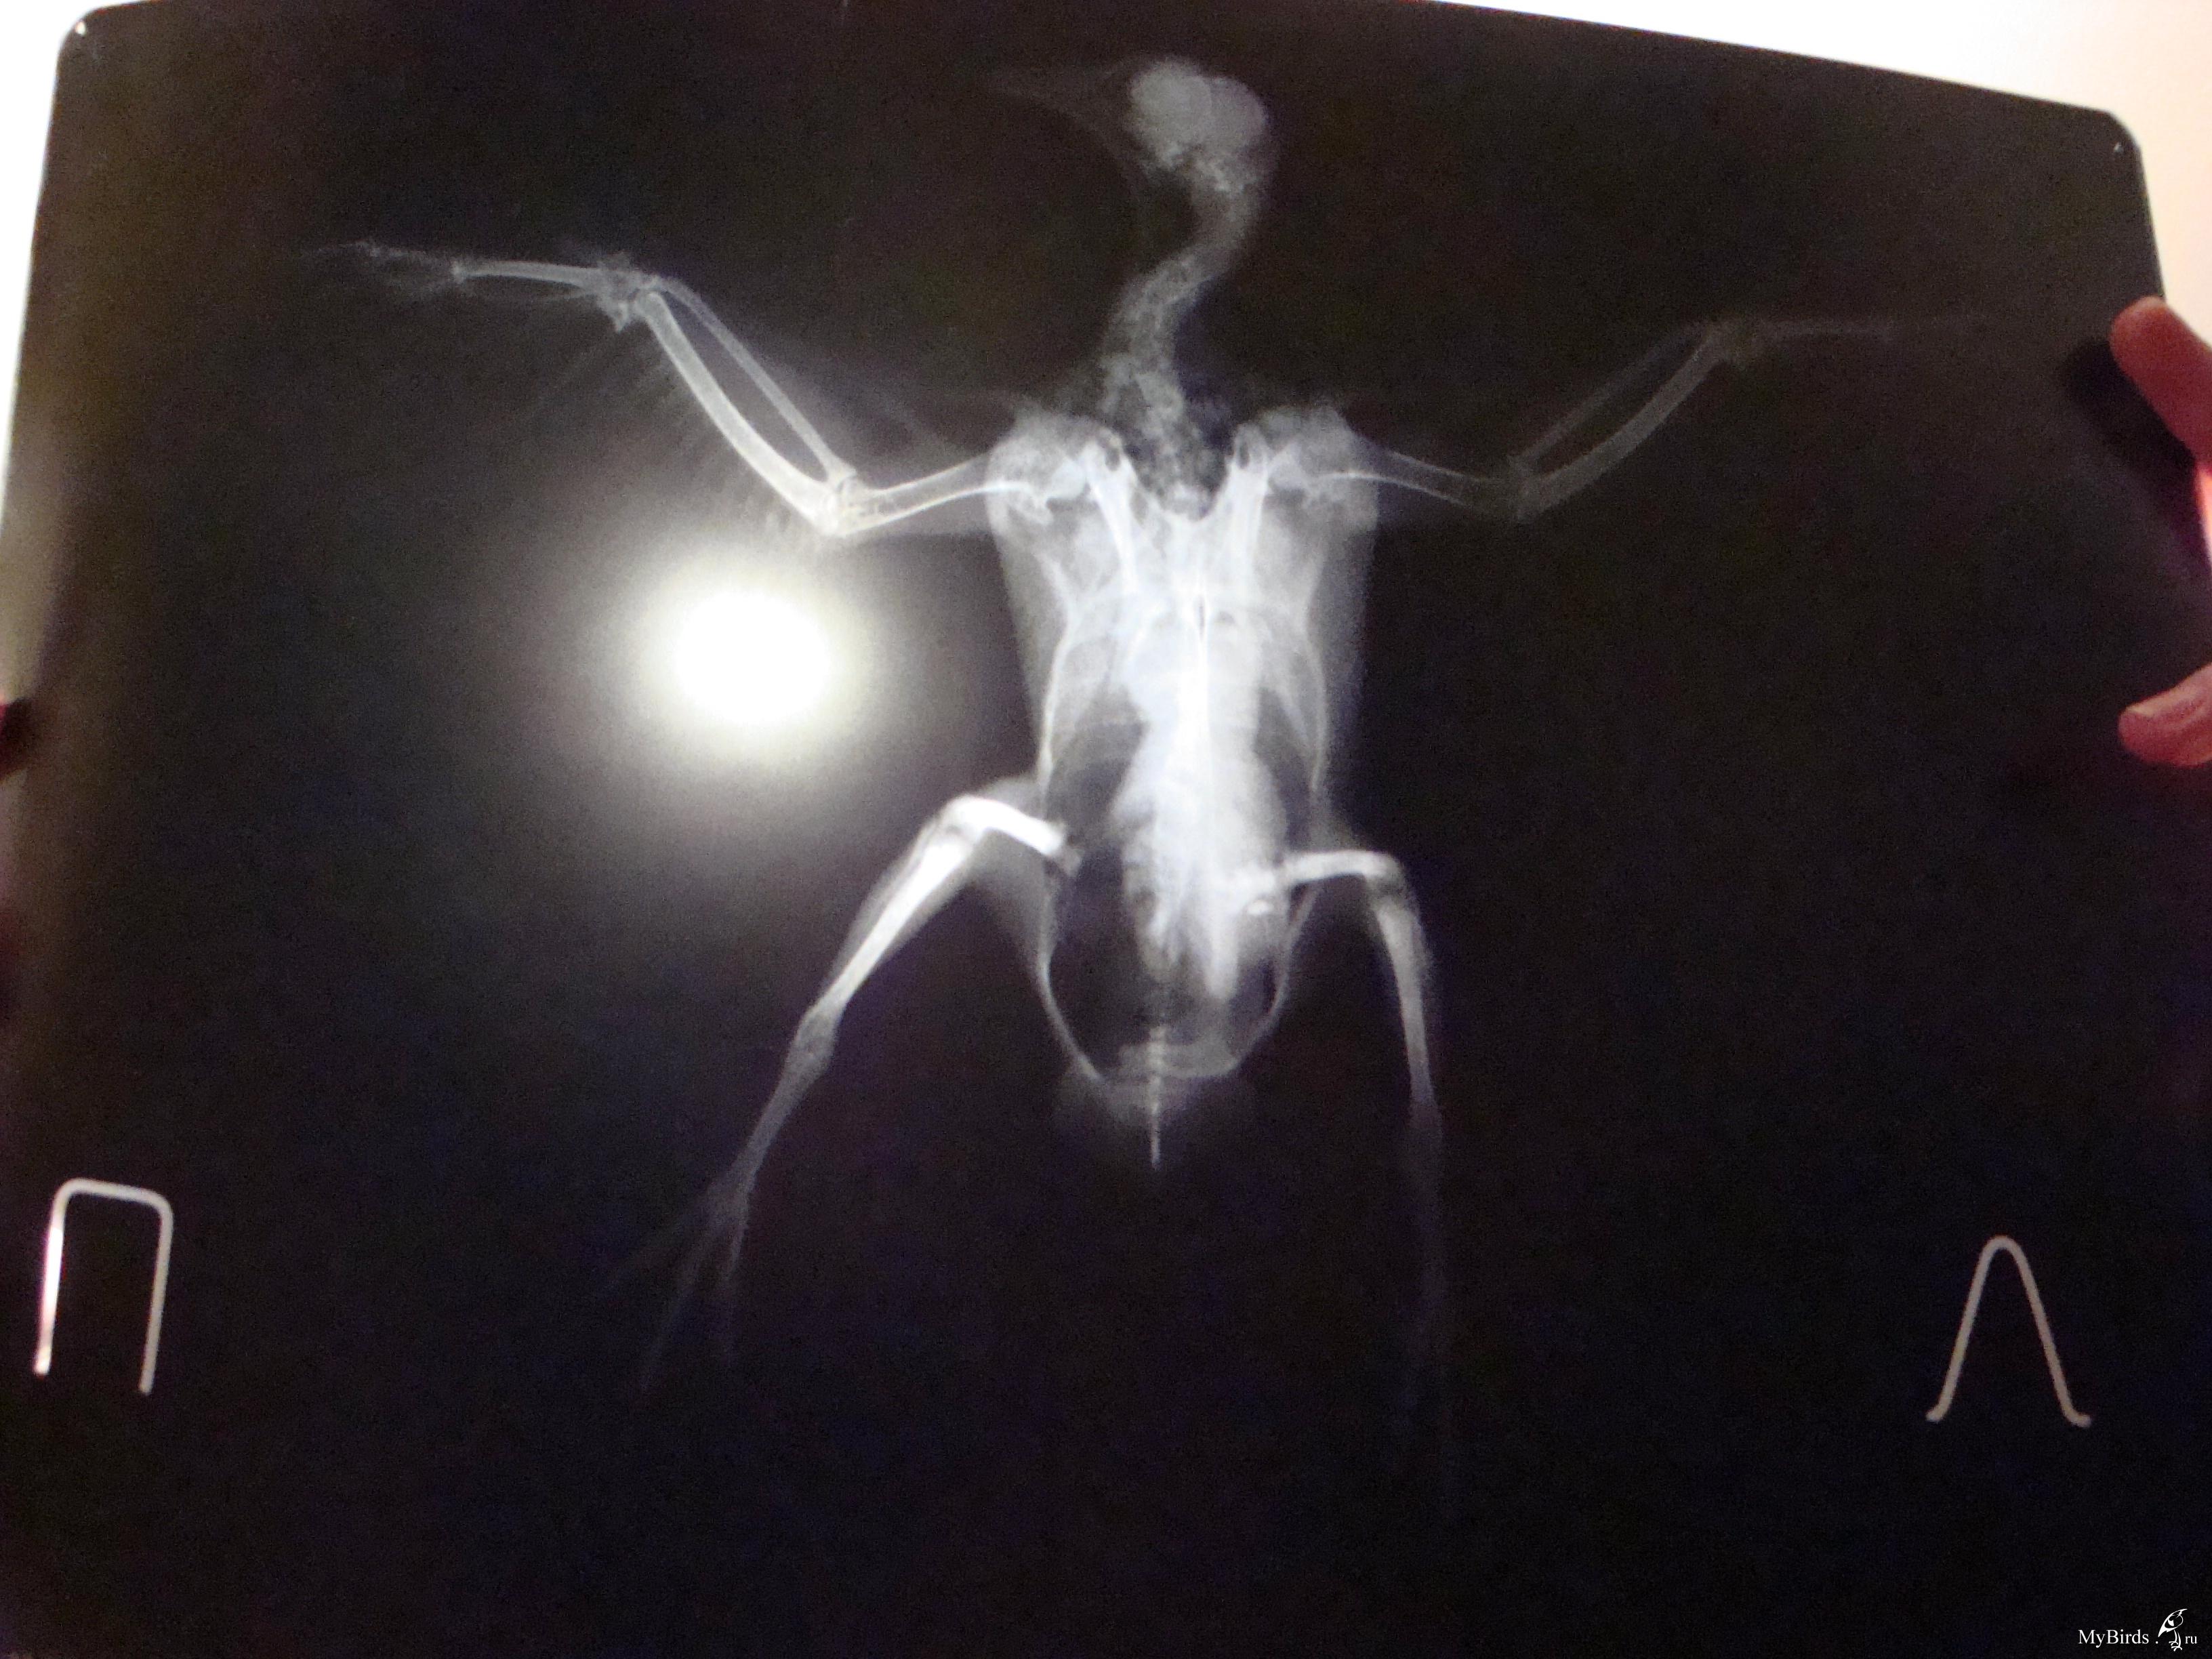

галина владимировна Опубликовано 11 сентября, 2009 Автор #118 Опубликовано 11 сентября, 2009 Это снимки Серого(тот,что с крылом).Хирург осмотрел крылья,проверил на рентгене и сказал,что перелома нет.У меня просьба.Пропишите пошагово ЧТО ДАВАТЬ,СКОЛЬКО И КАК ДОЛГО.Начиная с пробиотиков.И,если нужны витамины,то какие и тоже сколь.Схему лечения пропишите,пожалуйста,подробно(как для особо одаренных). Теперь Лапушка(тот,что с лапами).Для него такая же подробная нужна схема лечения.И чем протирать его гузку(попку).А то он лежит в своем помете часами. .Снимки,конечно ,оставляют желать лучшего.Но ,когда они были мокрыми,было видно хорошо.А высохли и изображение исчезло. У гули перелом обеих конечностей и перелом правого крыла.Хирург сказал,что крыло заживет само.А вот лапы..Переломы старые.Одна лапка сломана близко к суставу.Ее никто лечить не будет.А другую можно восстановить.Нужна операция. Операция стоит 6 тысяч.Помогите,пожалуйста, собрать средства!

Cheshirski Опубликовано 12 сентября, 2009 #120 Опубликовано 12 сентября, 2009 галина владимировна, поправил ваш пост с фотографиями - для удобства. Остальное - сейчас посмотрю-подумаю, и напишу. Снимки,конечно ,оставляют желать лучшего.Но ,когда они были мокрыми,было видно хорошо.А высохли и изображение исчезло.676983[/snapback] Маленький совет - просто вдруг в будущем пригодится. Снимки фотографировать лучше либо прямо на негаскопе (приспособление с подсветкой у врача в кабинете), либо на чем-то подобном дома (вроде светильника с лампами дневного света и молочным стеклом), а на худой конец - просто на окне, приклеив к стеклу скотчемза уголки, днем на фоне неба.Но ничего, и так все достаточно видно. Серенький. Да, переломов нет. Не видно и артроза - последствия сальмонеллы, к примеру - суставчики чистые (просто есть возможность сравнить - у меня есть снимок моего сальмонеллезника с артрозом). Тогда подвисание крыла - следствие ушиба или небольшого растяжения - они на снимке могут быть и не видны (сильные - видны в виде затемнения - притока крови к пострадавшему месту).Он не истощен? Пока кормите и добавьте в воду Ветом 1.1 - он есть? А в клюв ампульный препарат траумель, по такой схеме:Первый день приема - 2 капли в клюв каждые час.Второй день - 2 капли в клюв каждые 2 часаТретий день - 2 капли каждые 3 часа, и далее даете так, чтобы в день было не менее 3-4 приемов. Можно еще и крыло мазать траумелем (мазь), но если перьев много - то не стоит - оперение замаслится.И посмотрим за состоянием. Лапушка. Перелом крыла - да, такой сам срастется, если крыльями очень махать не будет. Смещение есть, но небольшое, на локтевой кости около запястного сустава. Даже летать сможет, скорее всего. И не исключено, что прилично летать.Лапы.Правая - да, трудный перелом. Думаю, стоит все же зафиксировать его, примерно вот так:Здесь черным обозначены кости, красным - место перелома, синим - плотный материал, вроде плотного картона, вырезан по месту, его два куска - с обоих сторон лапы - снаружи и изнутри, между лапой и телом. Конечно, подсогнуть надо будет, чтоб лапку облегал. А зеленым - места фиксации этой шины лейкопластырем. Другой вариант - выгнуть нечто подобное из жесткой (стальной) проволоки, и тоже закрепить на лапе пластырем. Возможно, что-то и удастся сделать, чтоб лапа более или менее правильно срослась. Левая. Тут попроще, кость сломана почти в середине. Что за операцйия предполагается? Остеосинтез - то есть, установка спицы? Попробуйте с врачом поговорить - не удастся ли просто совместить перелом и тоже наложить шину? Дело в том, что остеосинтез не всегда успешен у птиц - от многого зависит, и в любом случае, надо будет обеспечить неподвижность лапы, а со спицей это не всегда удается. Хотя, если у врача есть уверенность в результате - то можно попробовать. Про помет и т.д. При таких травмах не исключен и ушиб внутренних органов - той же печени. Плюс голодовка.Давайте ей траумель так же, как и Серенькому, и Ветом в воду тоже - по четверти чайной ложки на 100 мл поилки. Плюс карсил - по полтаблетки раз в день - это для печени, растолочь и давать в клюв разведенный водой до состояния кашицы.На кандиду картина не похожа, в крайнем случае - на нечто бактериальное. Пока не давайте, но имейте под рукой ципрофлоксацин 250 мг таблетки, наверняка еще остались. Если вдруг состояние кого-то из гуль будет хоть немного ухудшаться - давайте ципрофлоксацин в следующем разведении:1/2 таблетки развести в 4 мл воды, давать по 0,2 мл 2 раза в день в клюв. Если начнете его, то не прерывайте курс, давайте 10 дней. Если все же сделают остеосинтез - тогда надо будет поколоть другое лекарство, да и еще кое-что добавить, тогда и напишу. По поводу финансов - киньте в личку полный адрес, переводом сколько-то переправлю. ПС. В форуме, как правило, бываю каждый день. Так что не пропущу, единственно - не всегда удается отвечать оперативно.